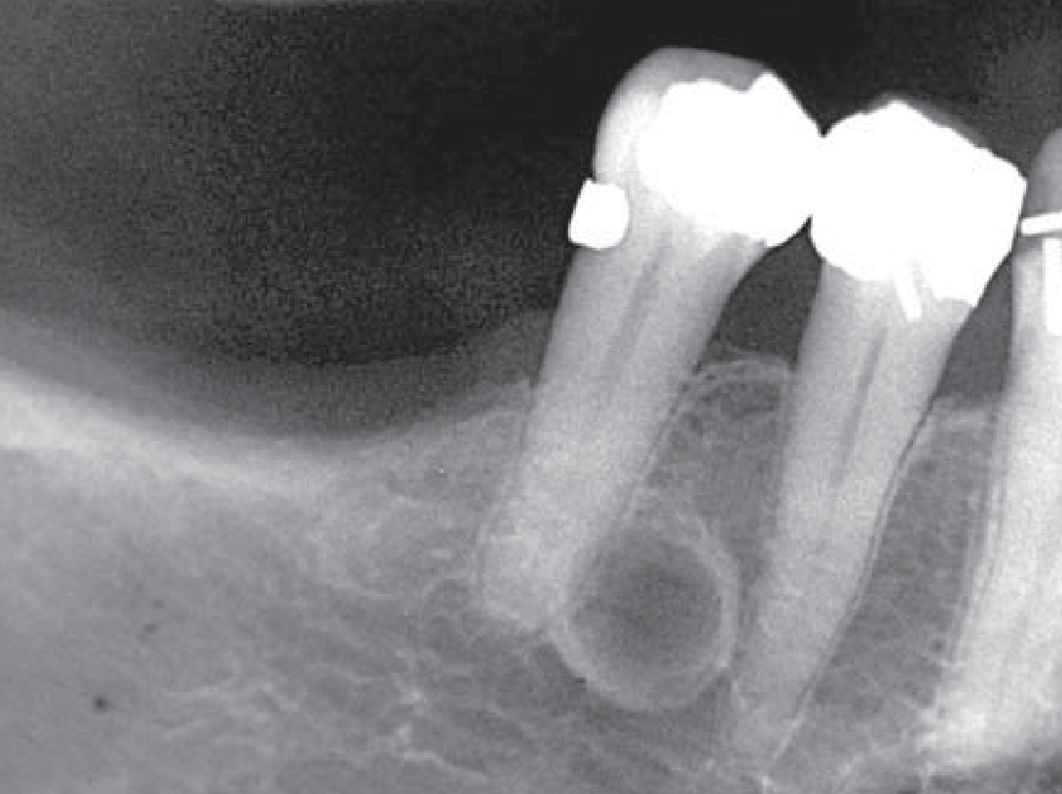

external resorption → irregular root surface

hypercementosis → bulbous-shaped roots

effects on adjacent teeth

tooth response mirrors bone response